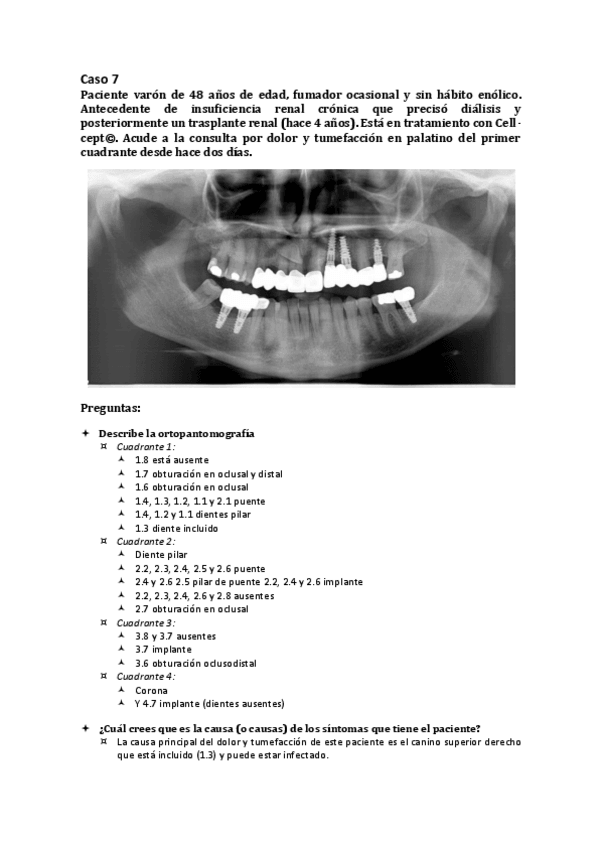

Caso-7.pdf